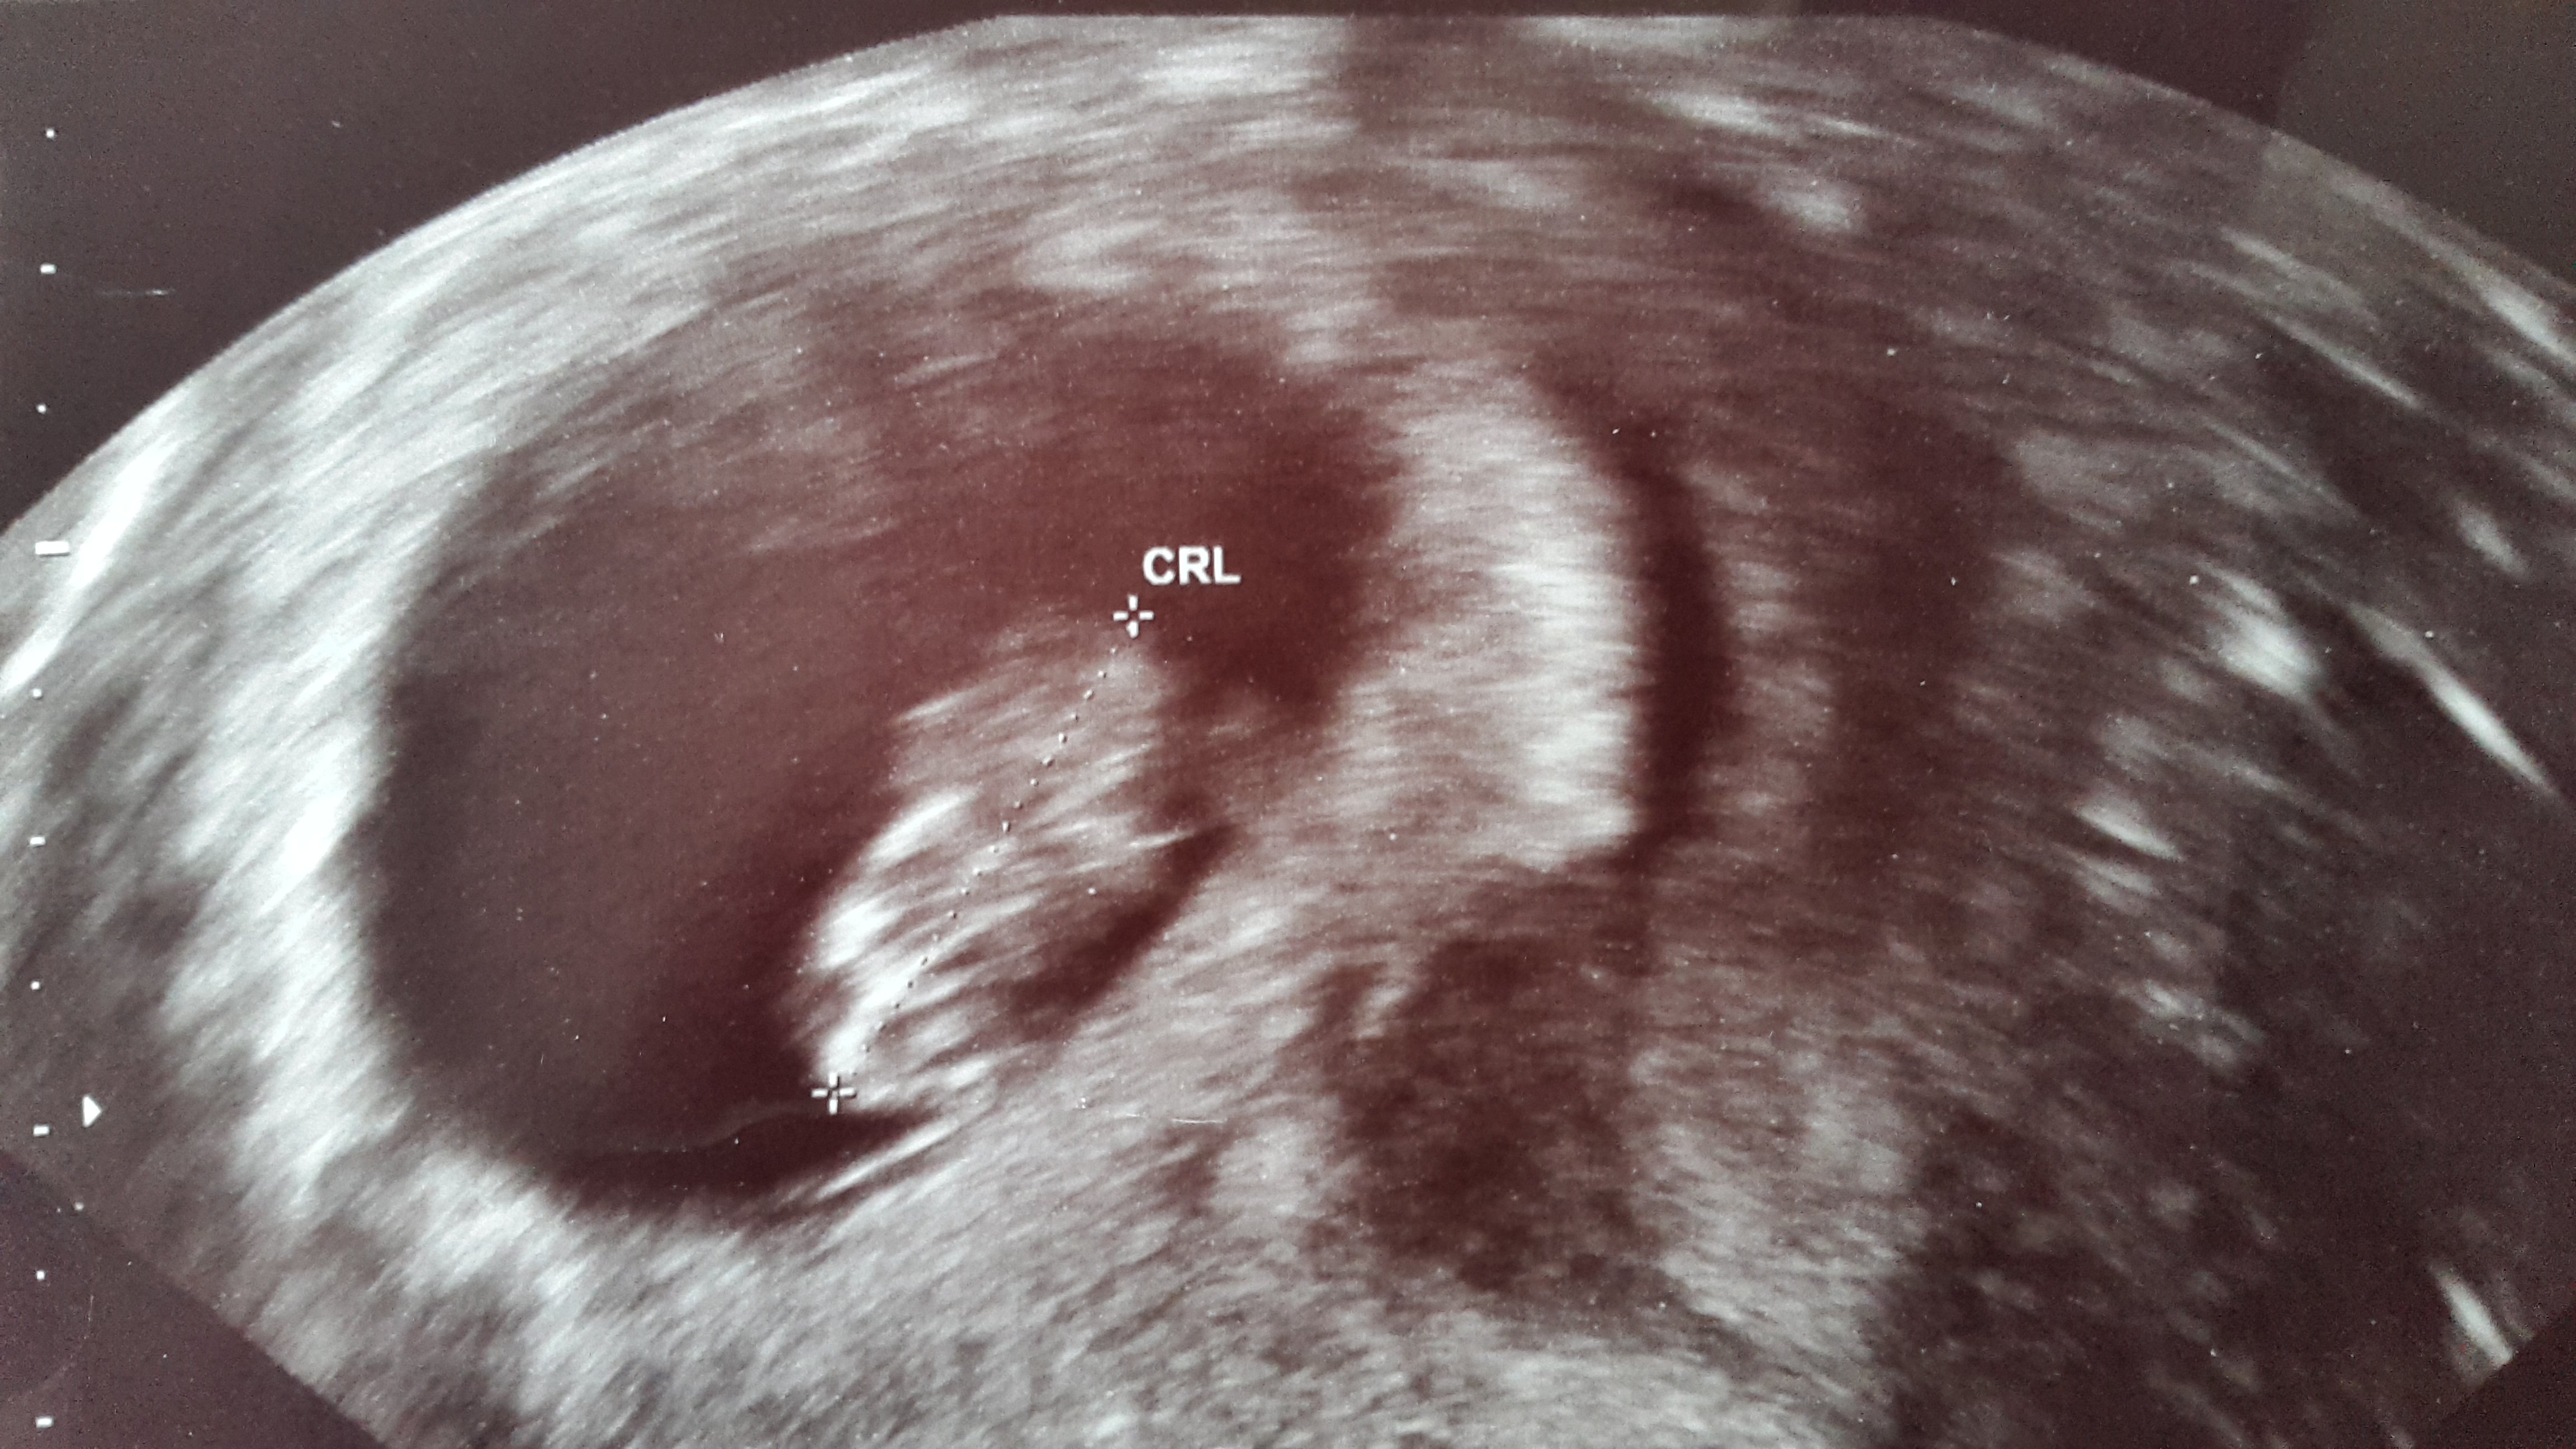

Our little peanut measured 7 weeks 1 day- a few days off, so our new due date is Dec 30. I am still a December birth month yay! Good heartbeat, very relieved and excited!

I thought I was 9 weeks today but am actually measuring at 8 weeks 3 days. My OB decided to keep the original due date since it's less than a week difference. Christmas Eve baby!

Taken at 8w6d but measuring 8w3d for now. We saw the heart flickering and the baby was waiving arms!! Cute Cute Cute, so happy! I go back in 3 weeks for another one.